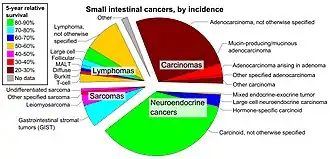

Histopathologic types

Subtypes of small intestine cancer include:[4]

- Adenocarcinoma – this cancer begins in the gland cells that line the inside of the intestine. Adenocarcinomas account for about 1 in 3 small intestine cancers.

- Gastrointestinal stromal tumor – this type of cancer starts in connective tissues. The most common sarcoma in the intestine are gastrointestinal stromal tumors (GISTs)

- Lymphoma – these cancers start in lymphocytes.

- Carcinoid tumors of the midgut – this is a type of neuroendocrine tumor (NET). They tend to be slow growing and are the most common type of small intestine tumor.

Most small intestine cancers (especially adenocarcinomas) develop in the duodenum. Cancers developed in the duodenum are often found at the ampulla of Vater.